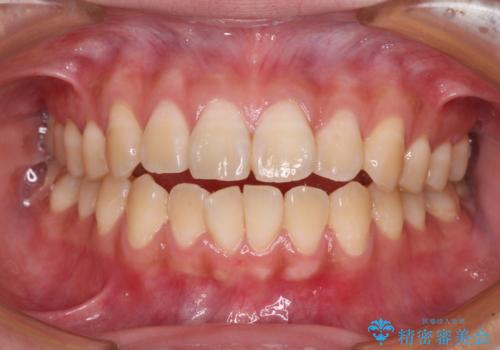

舌の突出癖による開咬と前歯の突出 インビザライン矯正治療

- 上下前歯の非接触と叢生を気にして来院された患者様です。

開咬の改善はインビザラインの最も得意とするところであるため、インビザラインを用いて矯正治療を行うこととしました。

治療開始直後に上顎前歯に激しい痛みが発現し、矯正治療を休んだり、マウスピースの装着時間を短くしたりと工夫をしましたが、残念ながら治療途中で失活していることが分かりました。

矯正治療の途中で前歯の根管治療とオールセラミッククラウンによる補綴治療を行い、その後インビザライン1セットを用いて細かい部分を仕上げました。